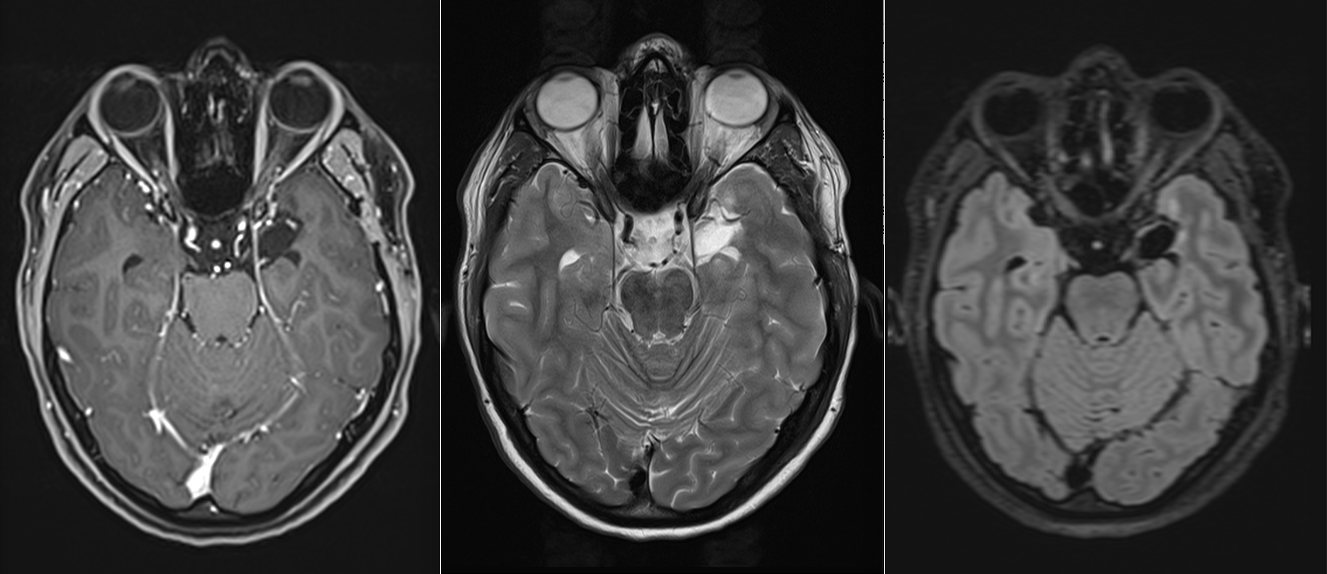

Pentru pacienți, aceste episoade sunt adesea greu de înțeles și pot fi însoțite de teamă și incertitudine. Investigațiile imagistice au adus însă explicația: RMN-ul cerebral a evidențiat o mică tumoră profundă, situată pe fața internă a lobului temporal stâng, la nivelul hipocampului și al nucleului amigdalian.

Primele imagini RMN realizate imediat după intervenție au confirmat absența complicațiilor. Câteva săptămâni mai târziu, un nou control imagistic a arătat clar rezultatul: tumora fusese îndepărtată în totalitate.